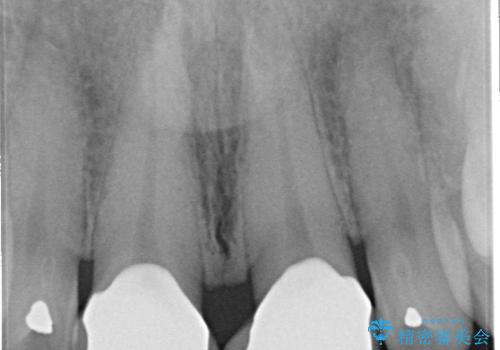

- 前歯のすきっぱを主訴にご来院された患者様です。他院でつめものやラミネートべニア(前歯の表面のみセラミックを貼り付ける)を行っていましたが、頻繁に外れることに悩まれており、クラウン(歯全体をセラミックがつつむ)をご希望されました。また、奥歯に大きな虫歯があり、歯が割れていたため、奥歯の治療も併せて行いました。

右上の歯に関しても、大きな虫歯があったため、前歯の経過観察の間に治療を行いました。